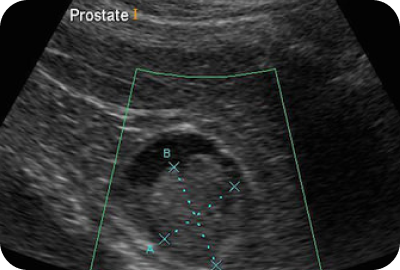

A real-time ultrasound is performed to evaluate the organs and structures in the lower abdominal area. This test is used to look at the bladder as well as the prostate gland and seminal vesicles to detect enlargements, cysts, masses, and any other abnormalities.